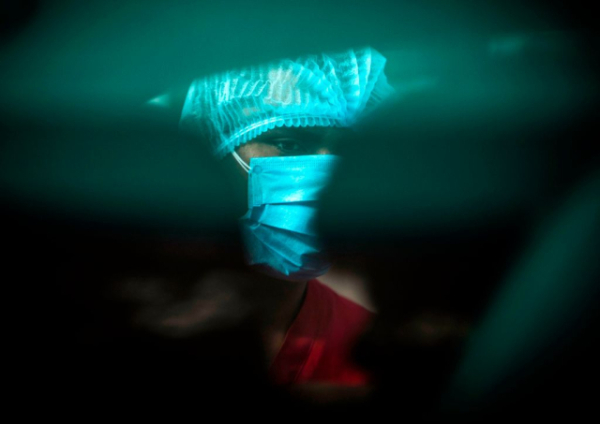

Enquanto a China anuncia a detecção de um vírus de alta contaminação, proveniente do contato com animais, no Brasil já são 680.598 óbitos e 34.065.650 casos conhecidos de Covid-19 registrados desde o início da pandemia, segundo dados reunidos pelo consórcio de veículos de imprensa.

O Brasil registrou nesta terça-feira (9) 359 mortes pela Covid-19 nas últimas 24 horas, totalizando 680.598 desde o início da pandemia. Com isso, a média móvel de mortes nos últimos 7 dias é de 219. Em comparação à média de 14 dias atrás, a variação foi de -4%, indicando tendência de estabilidade.